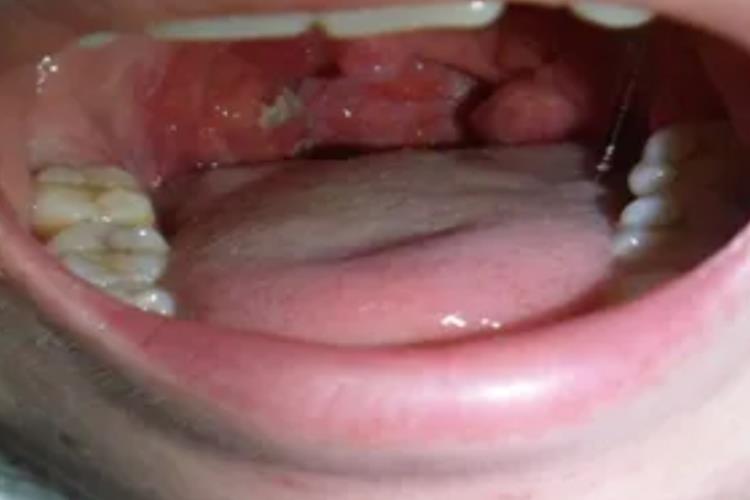

咽角化症患者可在常规口咽部检查时,见局部病变黏膜慢性充血,在扁桃体隐窝口有乳白色、尖头及一些碎片状角化物,呈笋样突出且质地坚硬,不易拔除。患者可表现为咽喉部有异物感、发痒、干燥、刺痛、不适感及声音嘶哑等症状。